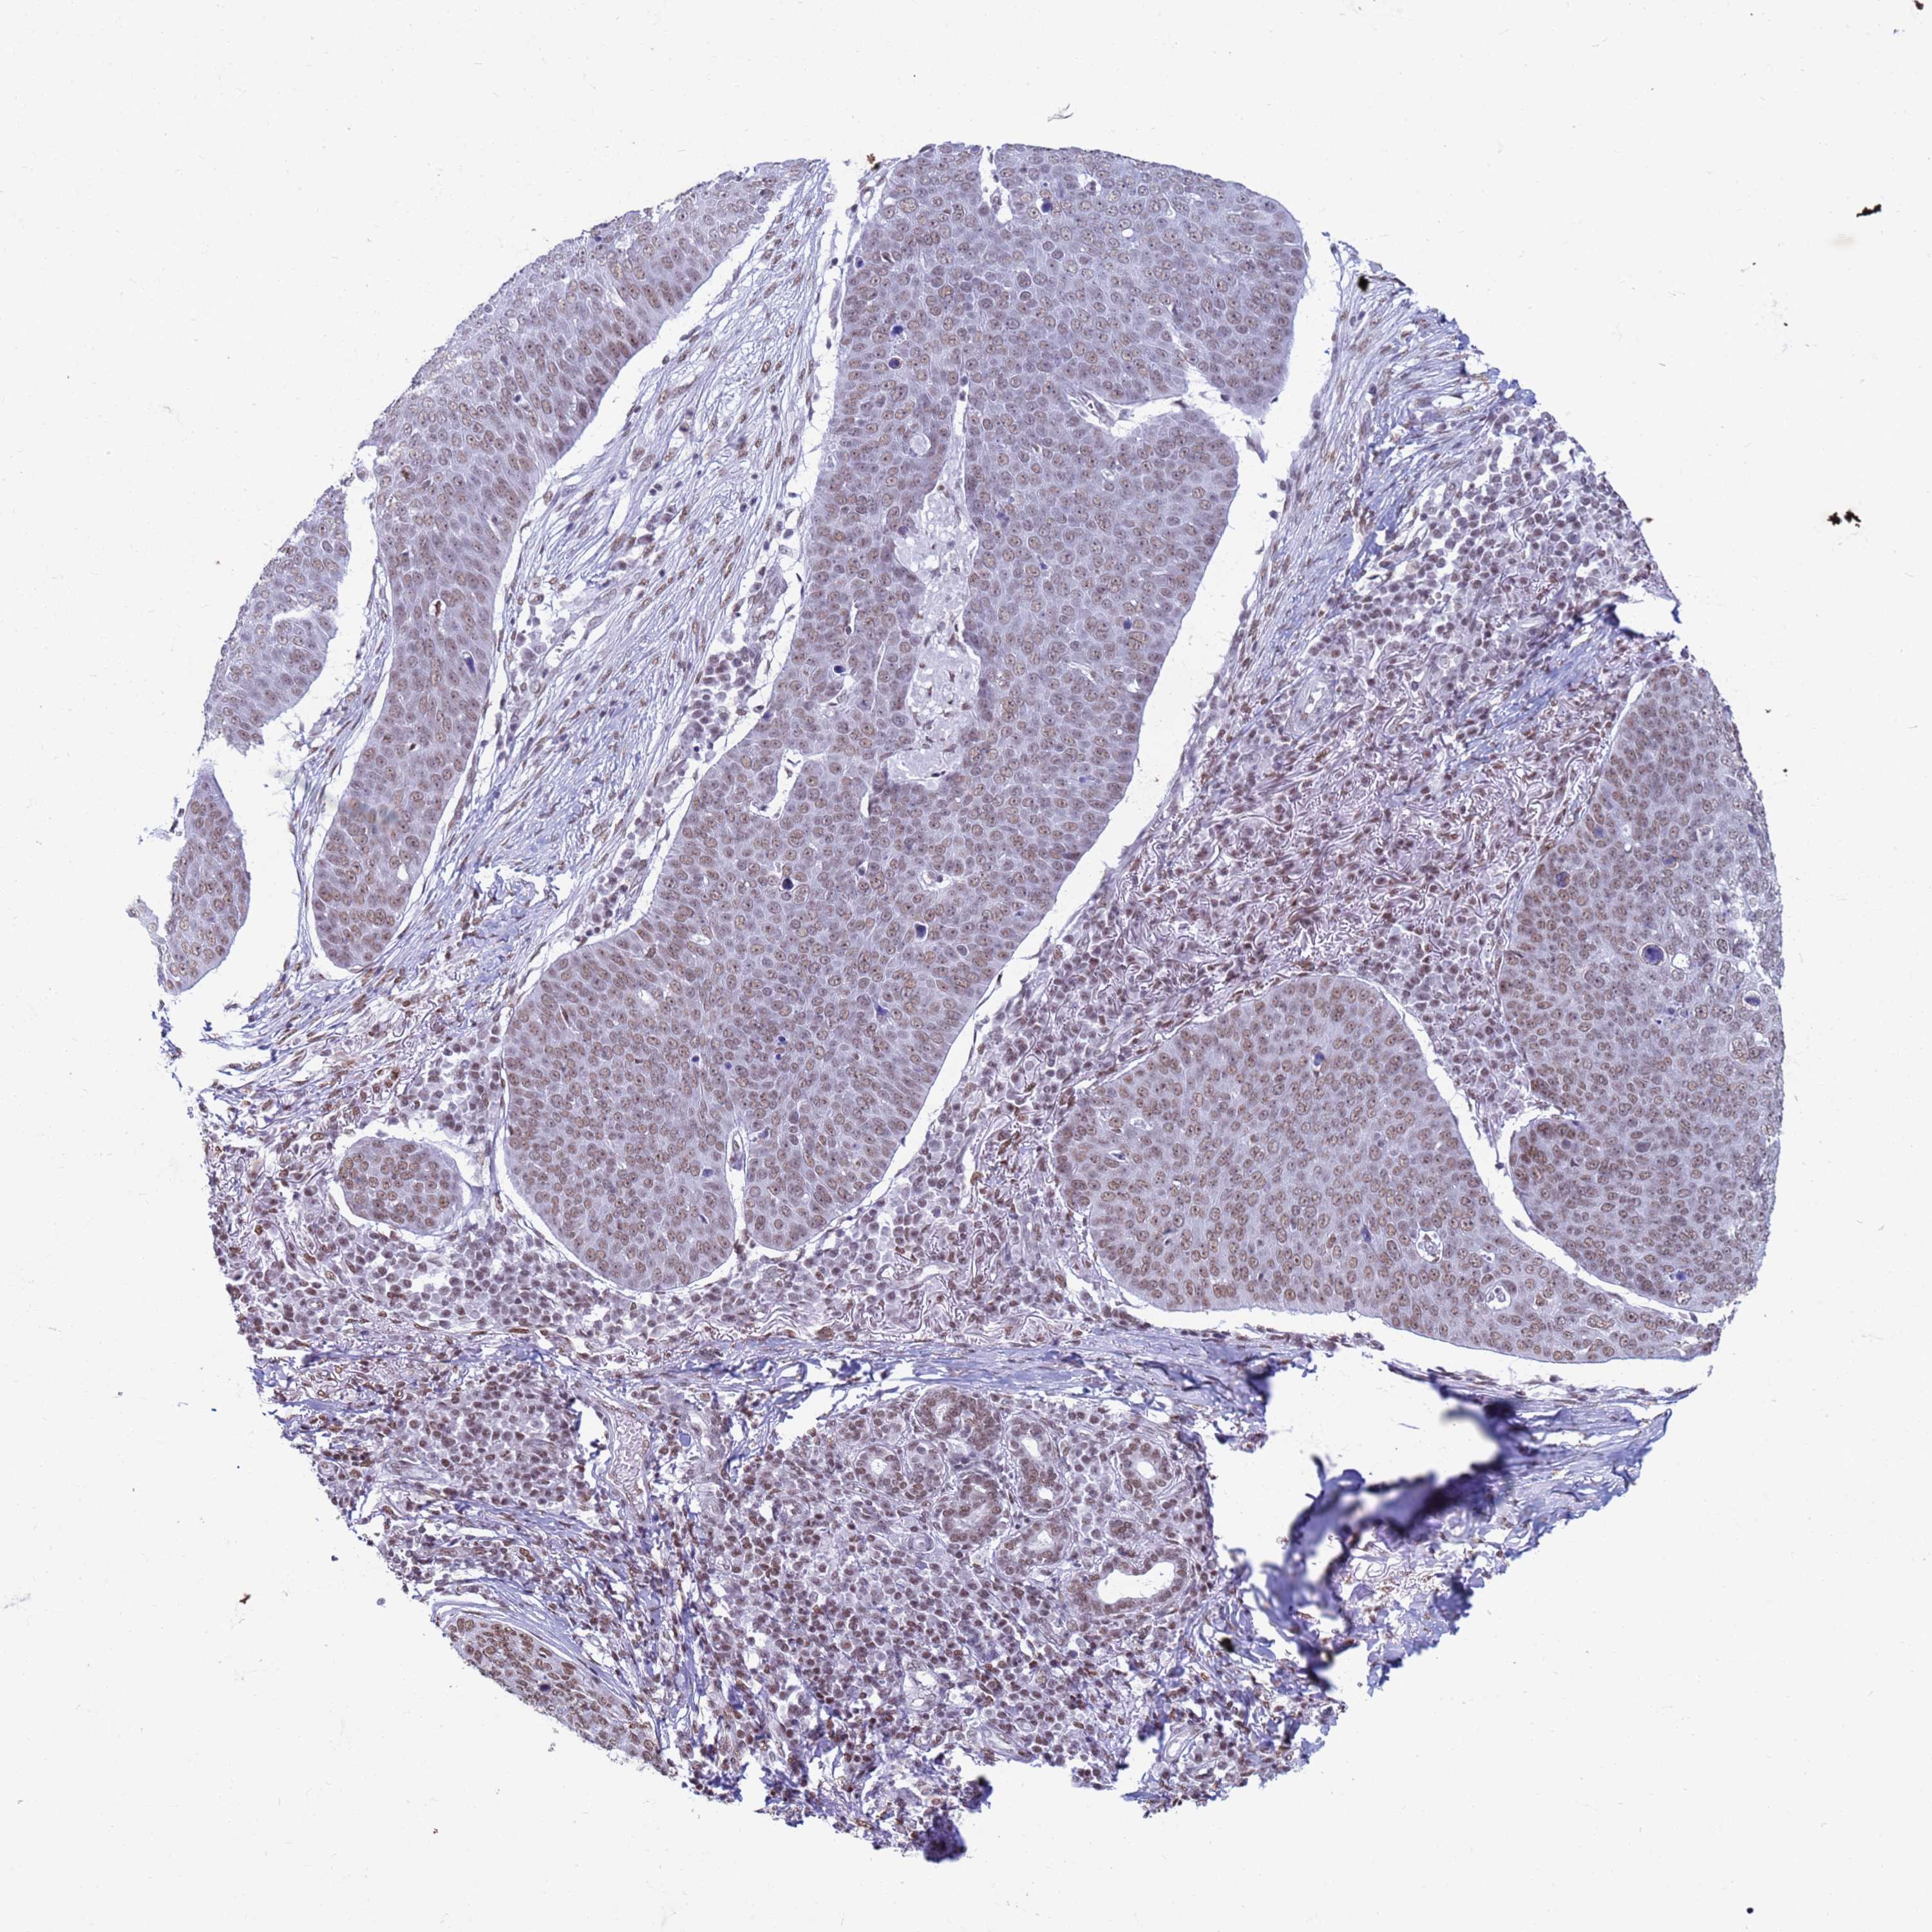

SKIN CANCER - Protein expressioni

A mouse-over function shows sample information and annotation data. Click on an image to view it in a full screen mode. Samples can be filtered based on level of antibody staining by selecting one or several of the following categories: high, medium, low and not detected. The assay and annotation is described here.

Antibody staining in the annotated cell types in the current human tissue is reported as not detected, low, medium, or high, based on conventional immunohistochemistry profiling in selected tissues. This score is based on the combination of the staining intensity and fraction of stained cells.

Each image is clickable and will lead to virtual microscopy that enables deeper exploration of all samples and also displays staining intensity scores, fraction scores and subcellular localization as well as patient and tissue information for each sample.

Antibody HPA043899

Basal cell carcinoma